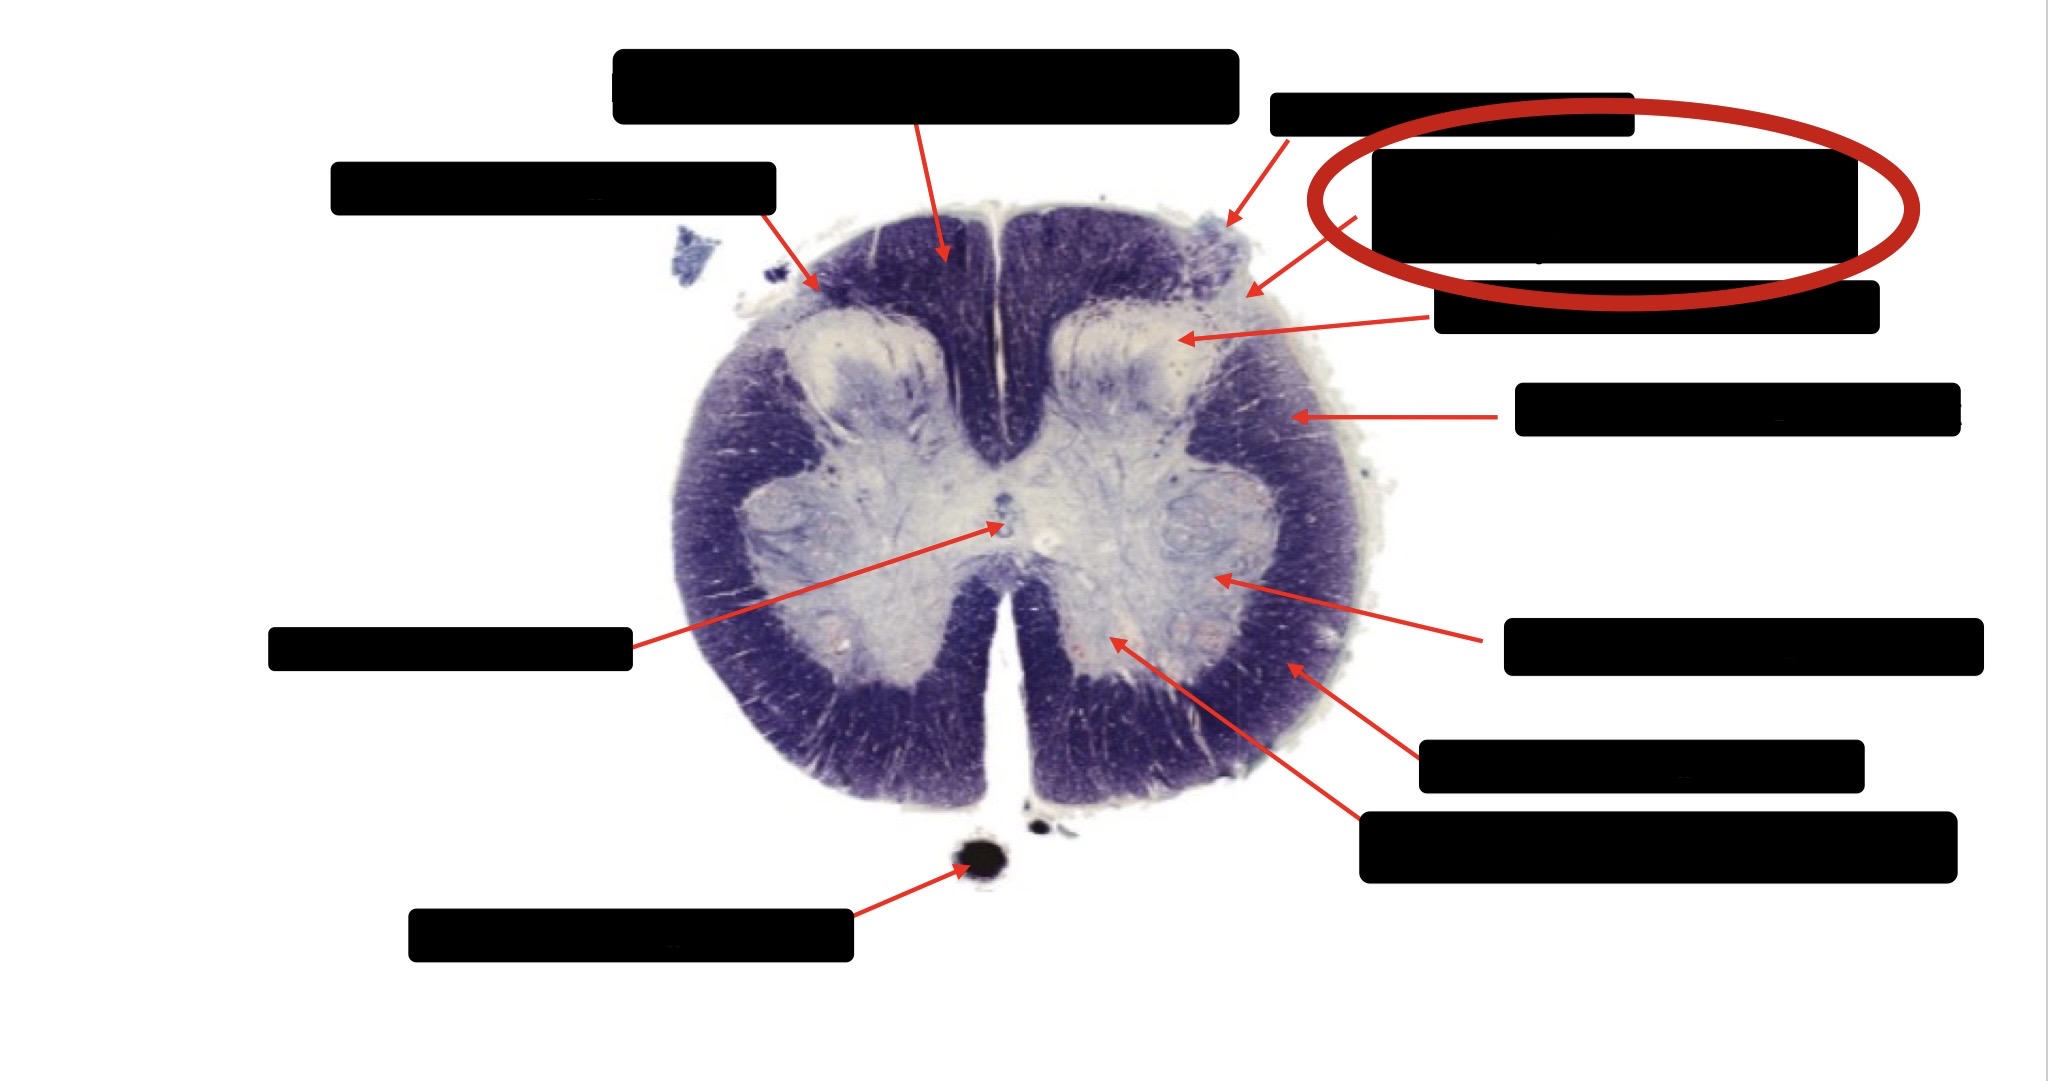

Posterior Column

Large Fiber Entry Zone

Posterior Spinocerebellar Tract

Clarke’s Nucleus

Anterior Spinocerebellar Tract

Ventral Root Fibers

Central Canal

Lissauer’s Tract & Small Fiber Entry Zone

Substantia Gelatinosa

Lateral Corticospinal Tract

Spinothalamic Tract

Anterior Horn Motor Neurons (Distal Muscles)

Anterior Horn Motor Neurons (Proximal Muscles)

Dorsal Rootlet

Lateral Horn